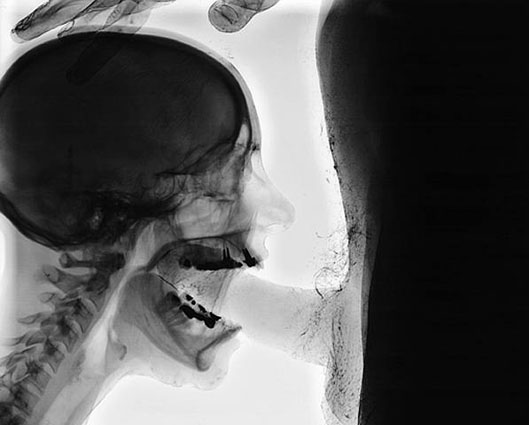

MudamSérie 9 muses (2001) : série de vitraux réalisés avec des plaques d'imagerie médicale aux rayons X eux-mêmes « X » puisqu'il s'agit de scènes pornographiques (fellation, coït).

Butt 1

La Rose des Vents